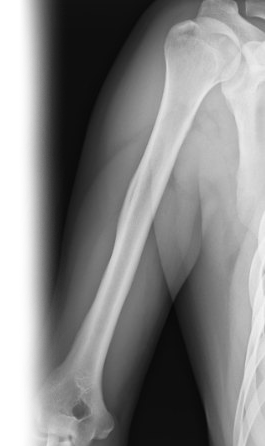

Рентгенография плечевой кости – важный метод прицельного исследования, который позволяет оценить состояние плечевой кости. Диагностическая услуга выполняется в двух проекциях.

Показания для проведения рентгена плечевой кости:

• травма, боль, отек в области плеча.

Рентген позволяет исключить патологию плечевой кости костно-травматического, опухолевого и воспалительного генеза.